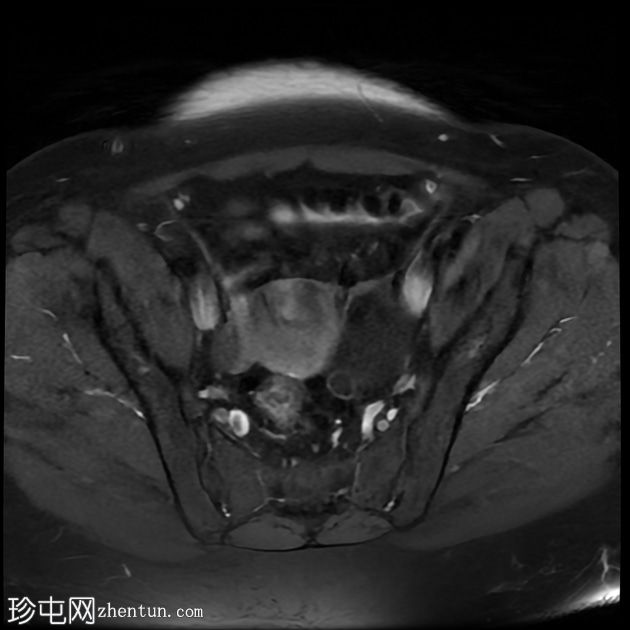

轴位T1加权像

增强脂肪抑制像

7.jpg

左侧卵巢增大,呈弥漫性低T1信号和高T2信号,可见周边卵泡,部分卵泡除周边卵泡周围有环状强化外,无明显实质强化。左侧附件蒂呈漩涡状,提示卵巢扭转。